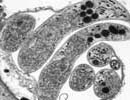

Cryptosporidium_hominis_33537 Courtesy of Saul Tzipori, Tufts

Comment:Cryptosporidium hominis is the dominant species which infects humans. Although generally self-limiting, this disease can cause fatalities in children and immunocompromised adults. The genome sequence of Cryptosporidium hominis shows features consistent with its life cycle as an obligate parasite. This organism lacks the genes necessary for the production of a number of biochemical building block such as nucleotides and amino acids. To compensate for this lack, the genome contains a large number of transporter or transporter-like genes.